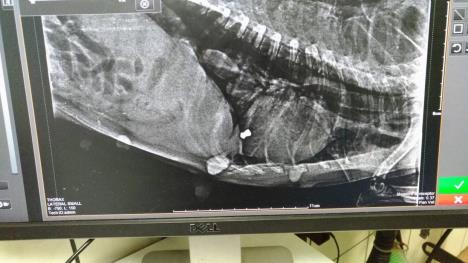

"Kada smo je ugledali, odmah smo je odneli kod veterinara. Ženka se gušila, ali smo uspeli da je spasemo. Veterinar ju je hitno operisao i izvadio metak", kažu iz ovog udruženja.